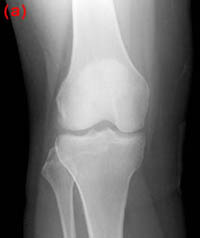

25) Name the abnormality shown in the image below.

26) How can a patellar fracture be distinguished from bipartite or multipartite patella?

27) A patient is known to have a torn ACL and presents for x-ray examination of the knee. Which of the following findings is often associated with a torn ACL?